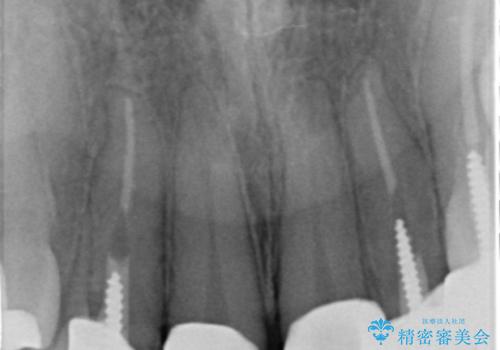

X線写真よりクラウンの際があっていない状態であることがわかり、再度精度の良いセラミッククラウンを製作していくこととなりました。

残存している歯と、クラウンの合いが悪い(不適合クラウン)歯汚れは溜まりやすく歯ぐきが腫れ虫歯・歯周病の再発リスクを高めます.